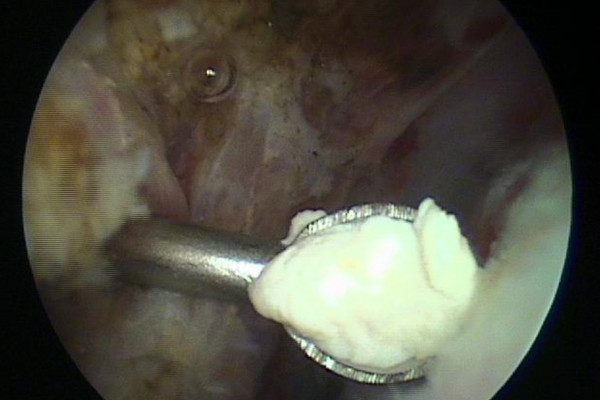

Der in der Sehne gelegene Kalkherd wird mit einer Hohlnadel (Bild 2) (der Kalk bleibt in der Nadelöffnung hängen) lokalisiert, danach wird der Kalk nach Eröffnung der betroffenen Sehne mit einem Löffel (Bild 3) möglichst vollständig entfernt und abgesaugt.